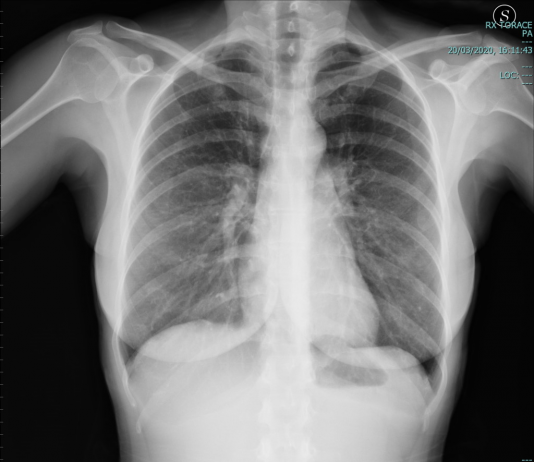

Maschio, 51 anni. Anamnesi patologica remota muta. Il paziente è residente a Fabrizia,...

Maschio, 51 anni. Anamnesi patologica...